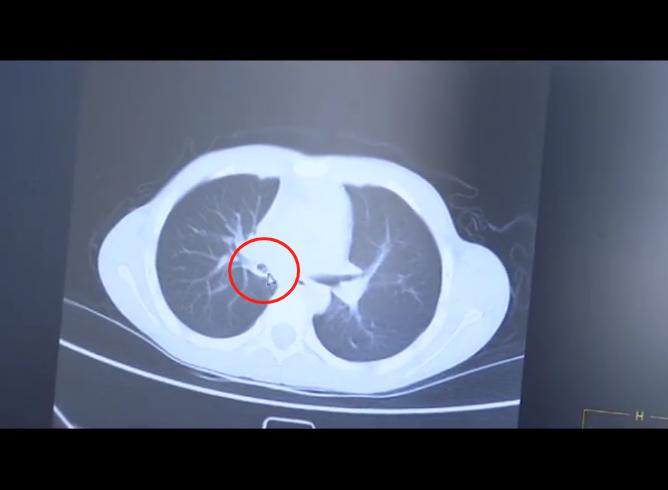

事发近2个月后,由于久治不愈,小罗的家长把他送到贺州市人民医院进行详细检查,经检查发现他的呼吸道里有明显异物。

9月11日,经过将近半小时的紧急手术,石螺壳被医生顺利取出。廖副主任说,他们医院每年接诊大概60多例气管存有异物的小孩,这种情况非常危险。